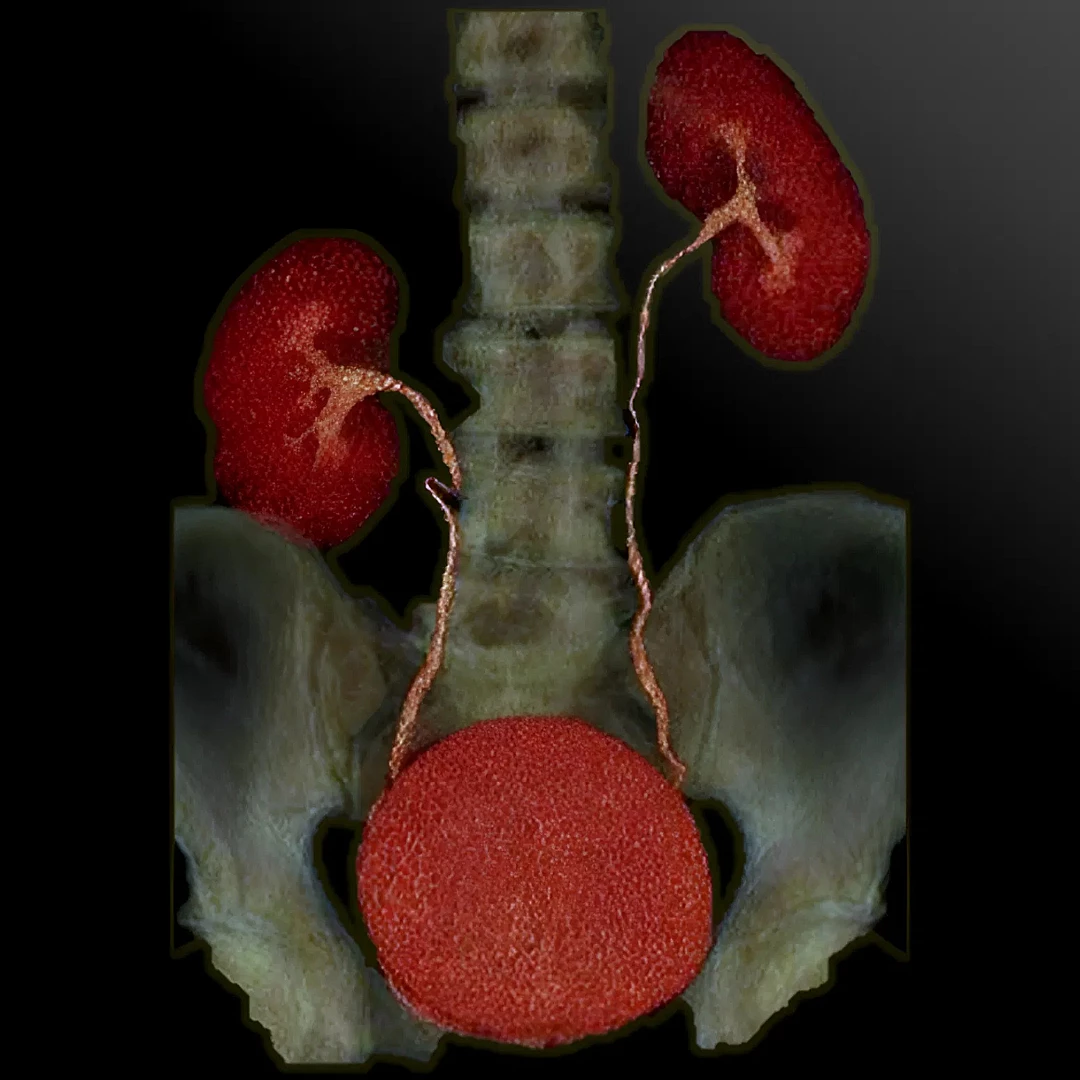

CT Urography provides detailed imaging of the kidneys, ureters, and bladder to detect stones, tumors, or urinary tract abnormalities. It’s a fast, contrast-enhanced scan ideal for comprehensive urinary system evaluation.